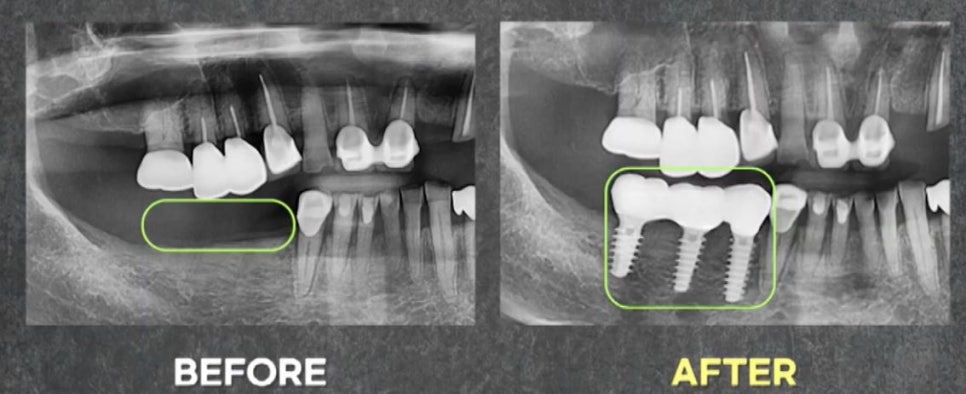

수술 당일 최종 보철까지 완성 후

엑스레이 사진입니다.

보통 임플란트 하면 몇 개월은 걸린다고

생각을 하고 계실 텐데요.

이렇게 무절개임플란트 수술을 하게 된다면

잇몸도 열지 않고, 뼈이식 없이

당일 최종 보철까지 가능하니

많은 환자분들께서 만족하는 시술입니다.